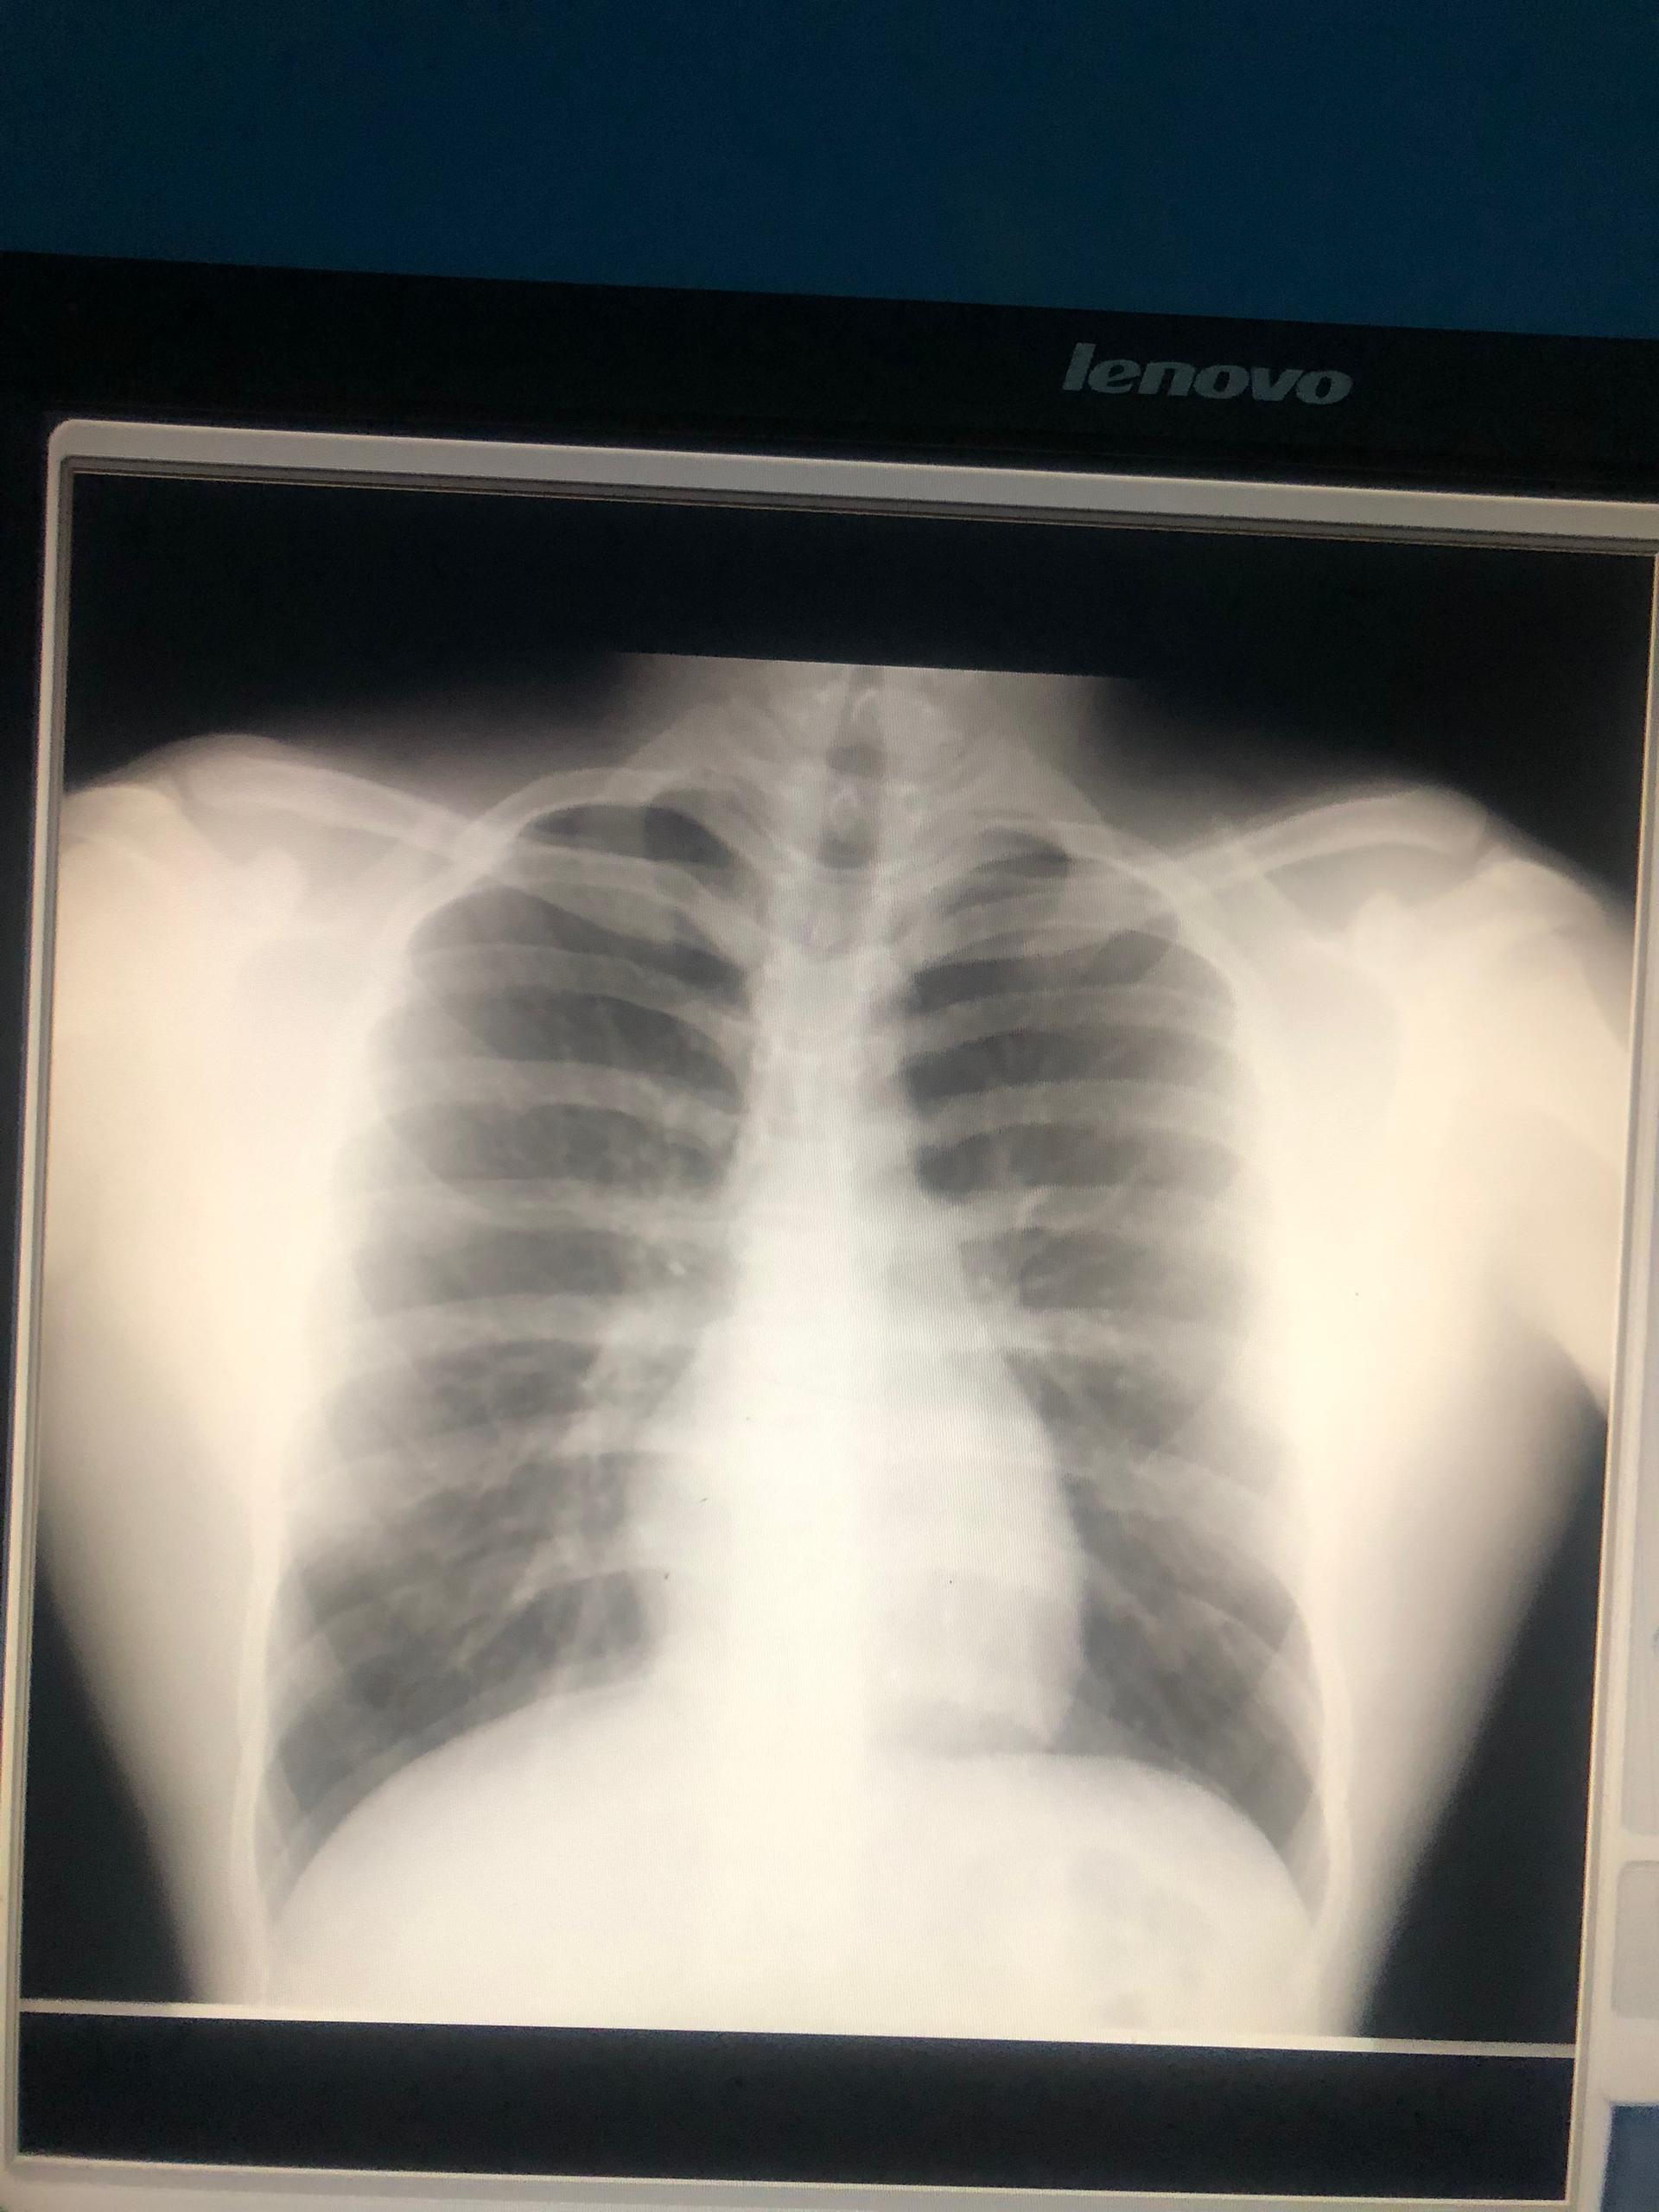

Fue una noche en que no se lo recomiendo a nadie, ni deseo a mi peor enemigo. Esto es una sensación que el simple hecho de toser, toser y no poder respirar es de lo peor. Esa noche me nebulicé para que pudiera entrar oxígeno y calmar la situación; sin embargo, sabía que tenía que ir al doctor para ver qué era lo que tenía. Primero fui al radiólogo, para hacerme una placa de rayos X. La chica, al ver mi placa, me comentó que era un patrón de neumonía que, si no me cuidaba, podría estar al borde de otro posible ataque.

It was a night I wouldn't recommend to anyone, nor wish on my worst enemy. It's a feeling that just coughing, coughing and not being able to breathe is the worst. That night I used a nebuliser so that oxygen could get in and calm the situation down; however, I knew I had to go to the doctor to see what was wrong with me. First I went to the radiologist to have an X-ray. The girl, upon seeing my X-ray, told me that it was a pattern of pneumonia and that if I didn't take care of myself, I could be on the verge of another possible attack.